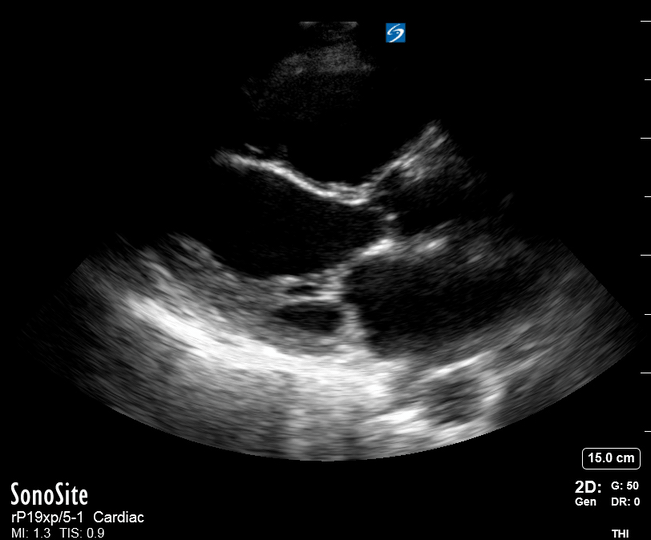

THE VIEWS

The A4C view provides an accurate chamber size comparison. However, achieving a proper A4C view (avoiding foreshortening or ballooning, and visualising the four chambers with a vertically oriented interventricular septum) can be a challenging exercise of image acquisition. Additionally, the PSAX view at the level of the papillary muscles shows both LV and RV side by side and is useful to assess function and size. When RV pressure is high, the septum will be pushed and flattened towards the LV, resulting in the characteristic “D-shaped” LV or “D sign”.

PITFALLS

When comparing size, beware of correct image acquisition, as oblique planes lead to misinterpreting the RV:LV ratio. For apical views be sure to slide the probe sufficiently laterally on the chest wall so that it lies over the true apex. Also, be sure to obtain a real horizontal plane, avoiding foreshortening (ballooning). For the PLAX view it is useful to fan through the heart’s long axis, making sure that LV visualization is maximized relative to the RV. Furthermore, an understanding of probe placement and marker orientation conventions is fundamental. If inadvertently scanning in reverse orientation, the normally larger LV could be mistaken for an abnormally enlarged RV.